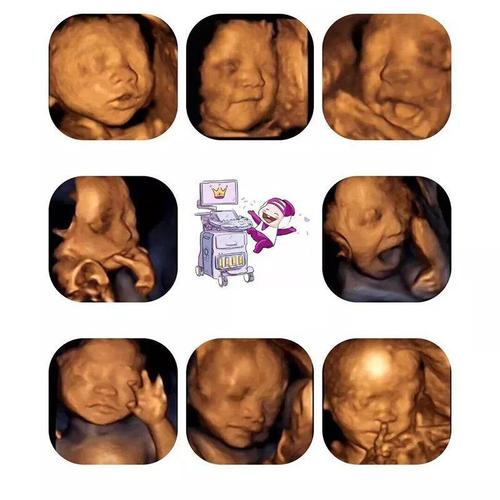

检查项目:血压、体重、宫高、腹围、胎心率、血尿常规、胎儿四维彩超+心脏彩超(20-24周)

检查目的:查看胎儿发育及是否畸形

检查说明:

建议提前约好四维彩超的时间,四维彩超的等待时间较长。排查畸形三维彩超和四维彩超都是可以的,但建议选择四维彩超,四维彩超可以更清楚看到宝宝身体各方面发育情况,筛查胎儿先天性疾病。

做四维超声时不需要空腹,可以在检查前多走动或进食巧克力,刺激胎儿活动,以便更加全面地进行检查。